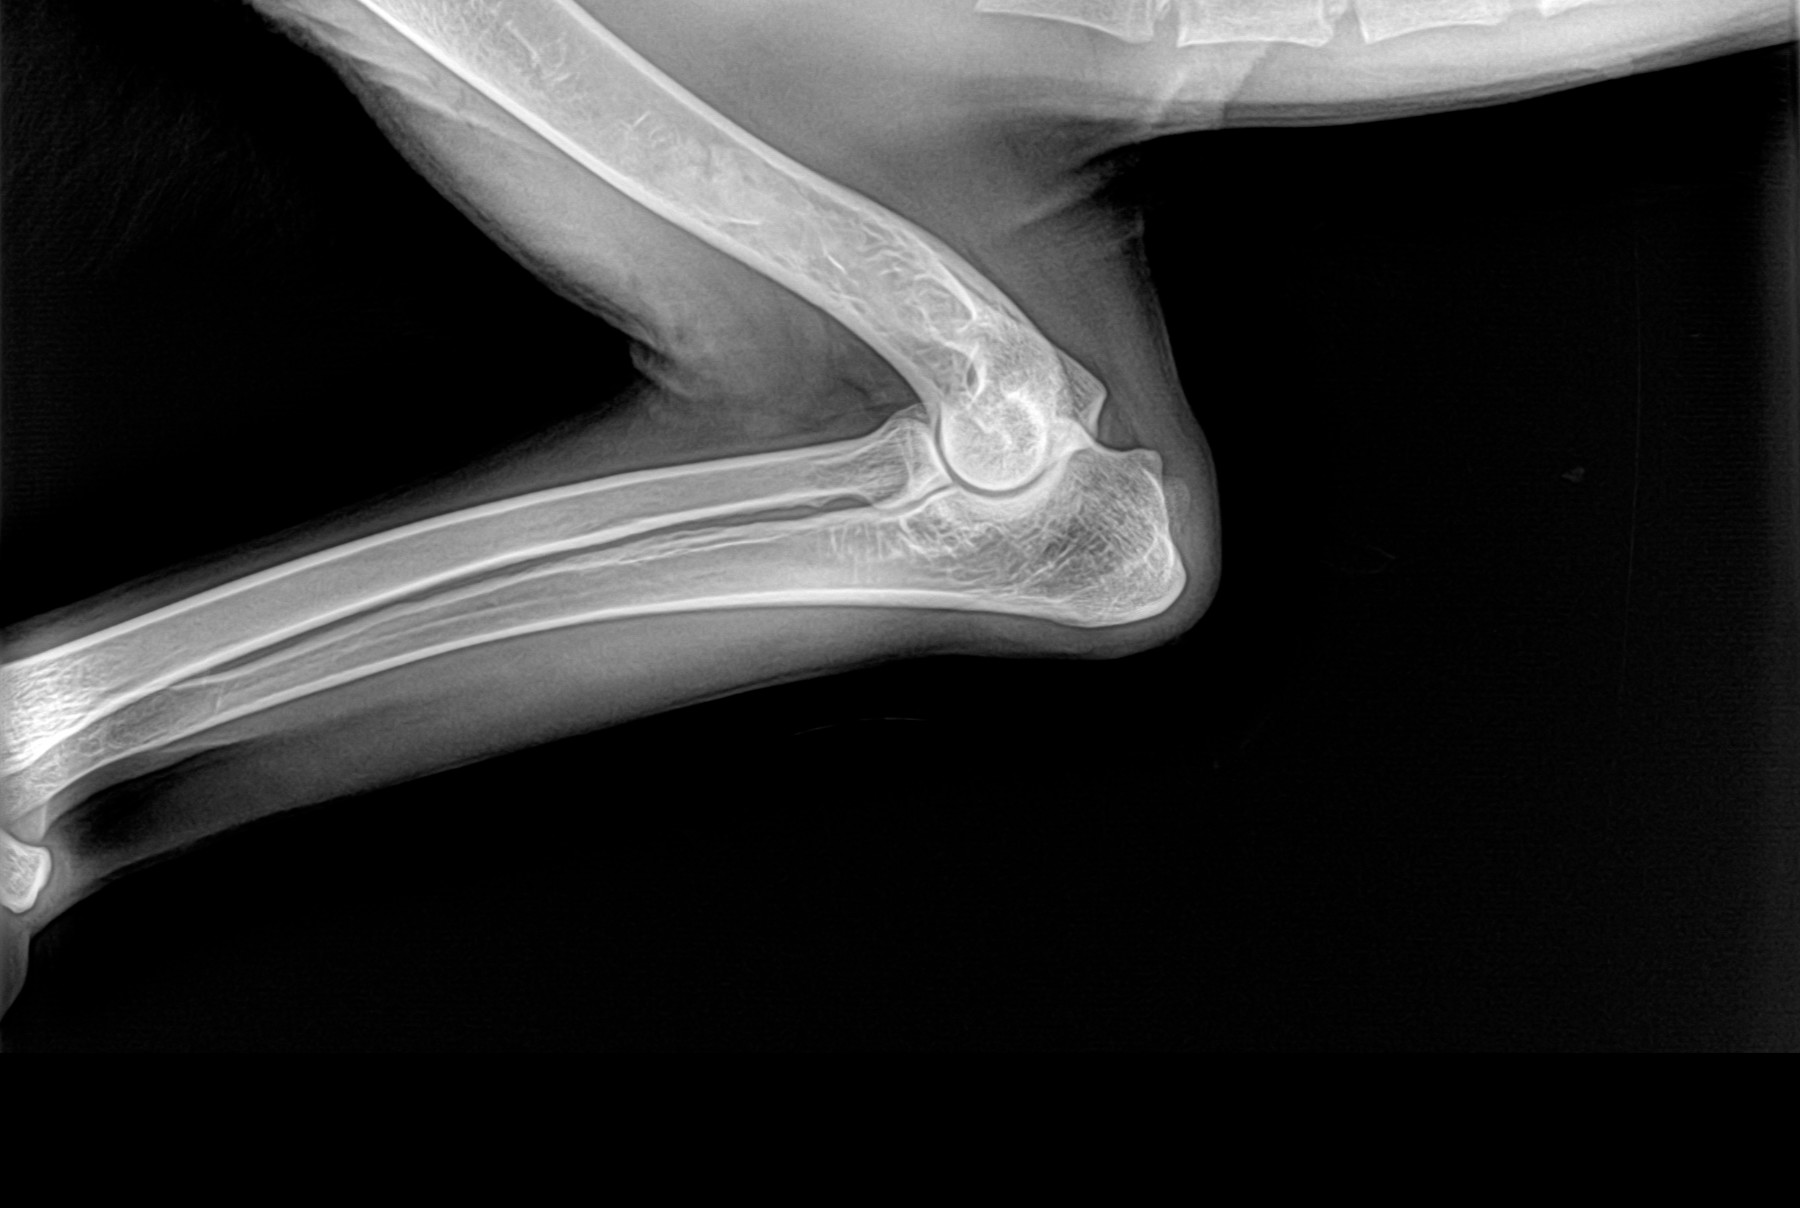

Cambios Térmicos en las Extremidades de Caballos,

Asociados a Golpes y su Evaluación por Termografía.

Los caballos de salto, en competencia, pueden derribar obstáculos y lastimarse. Si se golpean, no siempre claudican. Considerando al calor como un signo de inflamación, se evaluaron los cambios térmicos de 6 áreas de las extremidades torácicas y pelvianas de 23 caballos de salto en nivel de competencia de 1.05 a 1.60 m de altura, por medio de termografía durante 4 días de competencia (N=2208 áreas).